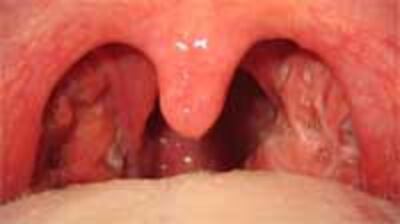

Amiđan là khối mềm, tròn, nhỏ nằm hai bên họng, được cấu tạo bởi mô bạch huyết (lymphoid tissue). Mô bạch huyết, là một thành phần quan trọng của hệ thống miễn dịch của cơ thể, có chức năng sản sinh ra các tế bào miễn dịch góp phần vào việc bảo vệ cơ thể.

Viêm họng, có người gọi là sưng họng, là phản ứng viêm của phần họng, thường bao gồm một phần ba sau của lưỡi, phần sau mềm của vòm họng, và amiđan.

Viêm là một phản ứng của cơ thể với các thành phần mà nó nghĩ là gây hại cho cơ thể. Phản ứng này thường gồm các triệu chứng sưng, nóng, đỏ, đau của vùng bị viêm. Bỡi vì amiđan là một thành phần nằm trong họng, viêm họng thường cũng làm viêm amiđan (còn thường được gọi là sưng amiđan).

- Trong viêm họng đo vi trùng strep, đau họng có thể đi kèm với sốt, nuốt đau, uể oải, nhức đầu, sưng đỏ họng, tiết đóng chất nhầy ở lưởi và amiđan, sưng đau hạch ở phía trước cổ; trẻ em có thể bị buồn nôn, ói mữa, đau bụng.